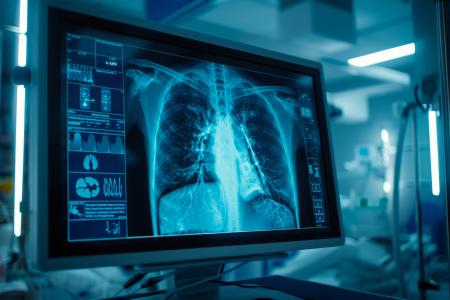

CANCER du POUMON : Il ne doit plus être synonyme de peur et de stigmatisation

C’est le message principal de ce numéro spécial du Journal of the American College of Radiology, qui met en lumière l'évolution de la perception du cancer du poumon : la maladie est devenue « traitable, guérissable et devrait être considérée comme une autre maladie chronique ». Ce bilan sur la maladie, effectué du point de vue radiologique, incite aujourd’hui à un effort concerté pour déconstruire la stigmatisation et la peur historiques associées à ce cancer, et à les remplacer par un message d'espoir.